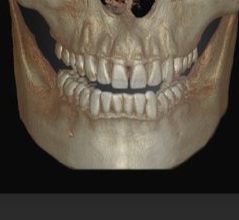

finger used as guide to where ramus ends

finger used as guide to where ramus ends